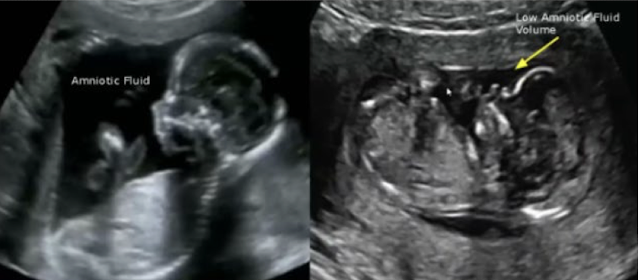

which has subjectively less AF?

right image